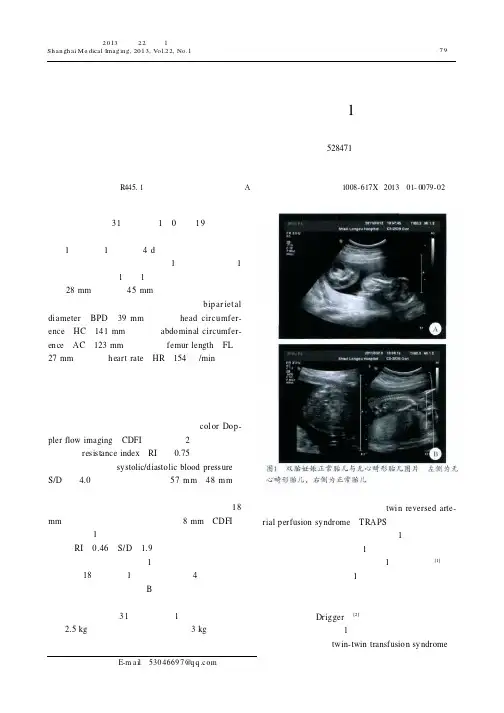

超声所见:增大子宫内可见1正常胎儿图像及1异常胎块图像(图1)。

1个胎盘附着于子宫后壁,厚约28mm ;羊水深45mm ,内未见分隔羊膜带回声。

正常胎儿生长指标如下:双顶径(bipar iet al di ameter ,BPD )39mm ,头围(head circumfer-ence ,HC )141mm ,腹围(abdominal circumfer-ence ,AC )123mm ,股骨长(femur length ,FL )27mm ,心率(heart rate ,HR )154次/min 。

正常胎儿各系统超声观察:颅骨环完整,脑中线居中,小脑无明显异常,上唇线未见连续中断,四肢、脊柱未见异常;胎心四腔观可显示,基本对称,十字交叉存在,心胸比例正常;腹壁完整,肝、胃、双肾、膀胱可见。

彩色多普勒血流成像(col or Dop-pler flow imaging ,CDFI ):脐动脉2支,脐血流阻力指数(resistance index ,RI )为0.75,脐动脉收缩压与舒张压比值(systolic/diastolic blood pressure ,S/D )为4.0。

异常胎儿:大小为57m m ×48m m ;无正常颅骨结构,无胎心搏动,可见连续脊柱及下肢长骨回声,胎儿全身弥漫性水肿,最厚处18mm ,腹腔内可见无回声区,前后径8mm 。